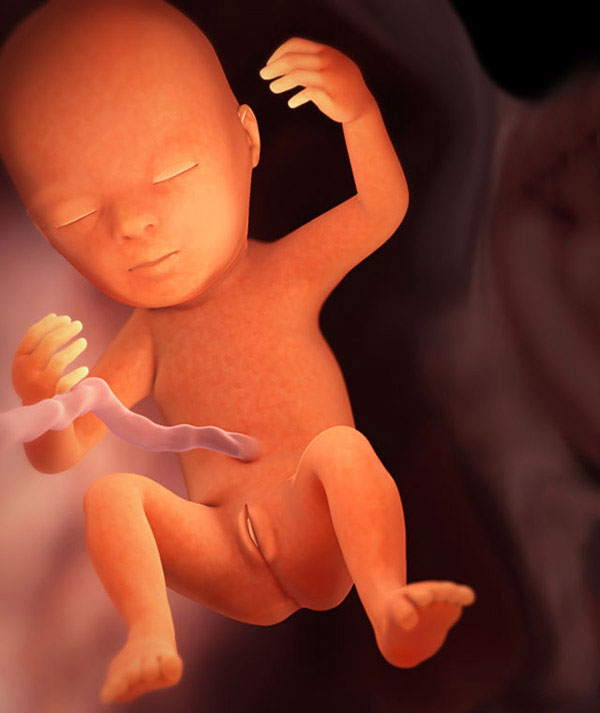

Vaisiai greitai auga. Atidarykite delną. Dabar jūsų kūdikis tiesiog tilptų ant jo. Štai taip vystosi jūsų vaikas:

tęsiasi skeleto mineralizacija, sustiprinami visi kaulai;

- raumenys vystosi;

- susidaro poodinių riebalų sluoksnis;

- išsivysto mažyčiai pirštų ir kojų pirštų sąnariai;

- vaisius dažnai „treniruojasi“, daro refleksinius judesius (čiulpia pirštą, pasisuka, imituoja kvėpavimą ir praryja amniono skystį);

- Virš mažų pieninių dantų užuomazgų iškyla vietiniai embrionai - gali praeiti daugiau nei keliolika metų, kol kai kurie iš jų išsiveržs!